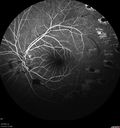

20 year old mane with fresh vitreous hemorrhage in the right eye. At age 15 he had a PPV and laser in the left eye and laser in the right eye. The vision is OD 20/80 PH 20/25, OS 20/25. The left eye has a mild cataract. He had prior testing for coagulopathies which was negative. Testing done for syphillis and TB was negative. Additional laser was done to prevent further bleeding in the right eye.